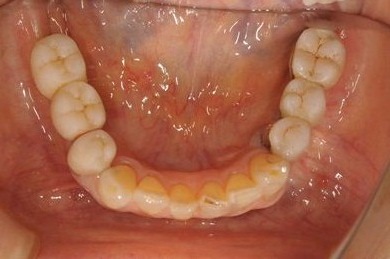

骨再生インプラント治療+セラミック治療

| カテゴリー | 【インプラント治療】【セラミック治療】 | ||||||||||||||||||||||||||||||||

| 性別/年齢 | 女性 / 53歳 | ||||||||||||||||||||||||||||||||

| 主訴 | 上のかぶせた歯にすき間があいてきた。インプラント治療も検討したい。 | ||||||||||||||||||||||||||||||||

| 治療内容 | インプラント6本(ソケットリフト)、ハイブリッドセラミック14本(ハイブリッドセラミック用土台5本、遊離歯肉移植術 | ||||||||||||||||||||||||||||||||

| 総治療費 | 2,751,445円 | ||||||||||||||||||||||||||||||||

| 治療期間 | 2年3ヶ月 |